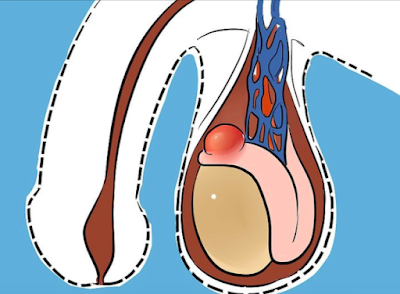

Quiste de epidídimo/Espermatocele

Quiste de epidídimo / Espermatocele

Un espermatocele (quiste en el epidídimo) es un quiste indoloro, lleno de líquido en el conducto largo y fuertemente enrollado que está encima y detrás de cada testículo. El líquido dentro del quiste puede contener espermatozoides que ya no están vivos. Se siente como un bulto liso y firme en el escroto, encima del testículo.

Aunque la causa del espermatocele a menudo se desconoce, es posible que sea causado por una obstrucción de los conductos que transportan los espermatozoides desde los testículos (conductos del epidídimo).

A menudo, un espermatocele no causa síntomas. Es posible que usted note algo que se ve o se siente como un bulto o masa por encima del testículo en un lado del escroto. O es posible que usted note un aumento general del tamaño del escroto. Los síntomas, cuando se presentan, pueden incluir dolor, hinchazón o enrojecimiento del escroto o una sensación de presión en la base del pene.

Por lo general, el espermatocele se diagnostica examinando el escroto. Como parte del examen, su médico alumbrará detrás de cada testículo (transiluminación) con una luz para detectar si hay masas sólidas que pueden ser causadas por otros problemas, como cáncer de testículo. Los espermatoceles están llenos de líquido, de modo que la luz pasará a través de ellos (transiluminación). La luz no pasará a través de las masas sólidas que pueden ser causadas por otros problemas, como cáncer de testículo. Es posible que se utilice un ultrasonido para confirmar el diagnóstico de un espermatocele.

Los espermatoceles por lo general no son peligrosos y se tratan solo cuando causan dolor o vergüenza o cuando disminuyen el riego sanguíneo al pene (poco frecuente). Por lo general, no se requiere tratamiento si un espermatocele no cambia de tamaño o se reduce a medida que el cuerpo reabsorbe el líquido.

Si el espermatocele se agranda o causa molestia, es posible que se requiera un procedimiento para extraerlo (espermatocelectomía).